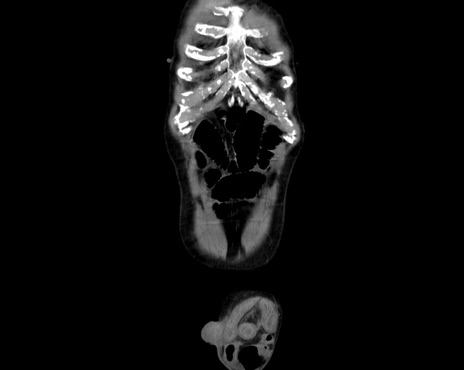

症例26(冠状断像)

【症例】80歳代男性

【主訴】嘔吐

【現病歴】昨晩2回嘔吐あり、今朝になっても嘔吐あり。来院。

【既往歴】胃潰瘍

【身体所見】意識清明、BT 37.6℃、BP 166/95mmHg、HR 100bpm、SpO2 97%、腹部:平坦・軟、腸蠕動音聴取良好、圧痛なし。

【データ】WBC 21900、CRP 1.4